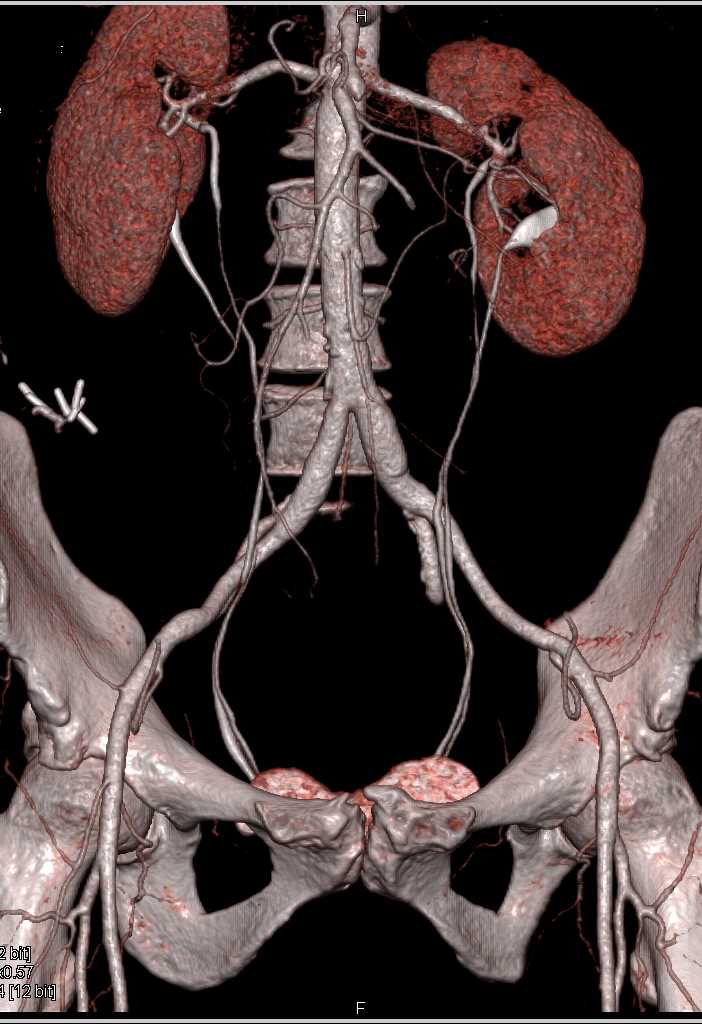

Diagnosis

SMA Stenosis